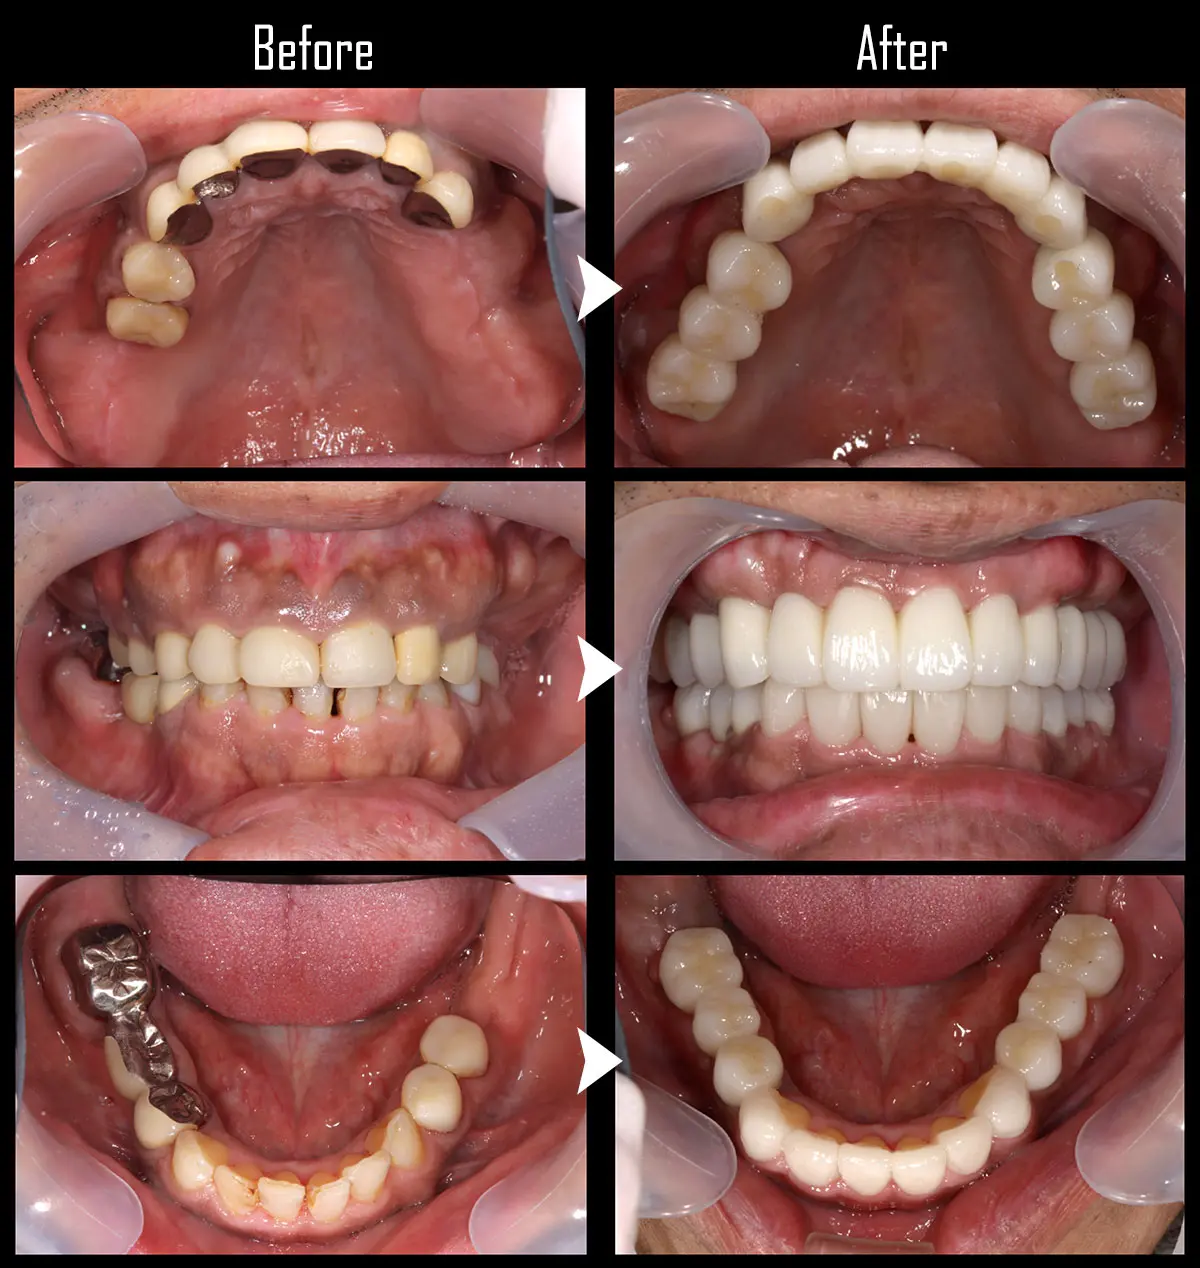

CASE:All-on-4(オール・オン・フォー)

症例All-on-4(オール・オン・フォー)

主訴 奥歯がない

治療内容 上下合計11本のインプラント治療を行い、全顎治療を実施

標準費用(自費) 781万円